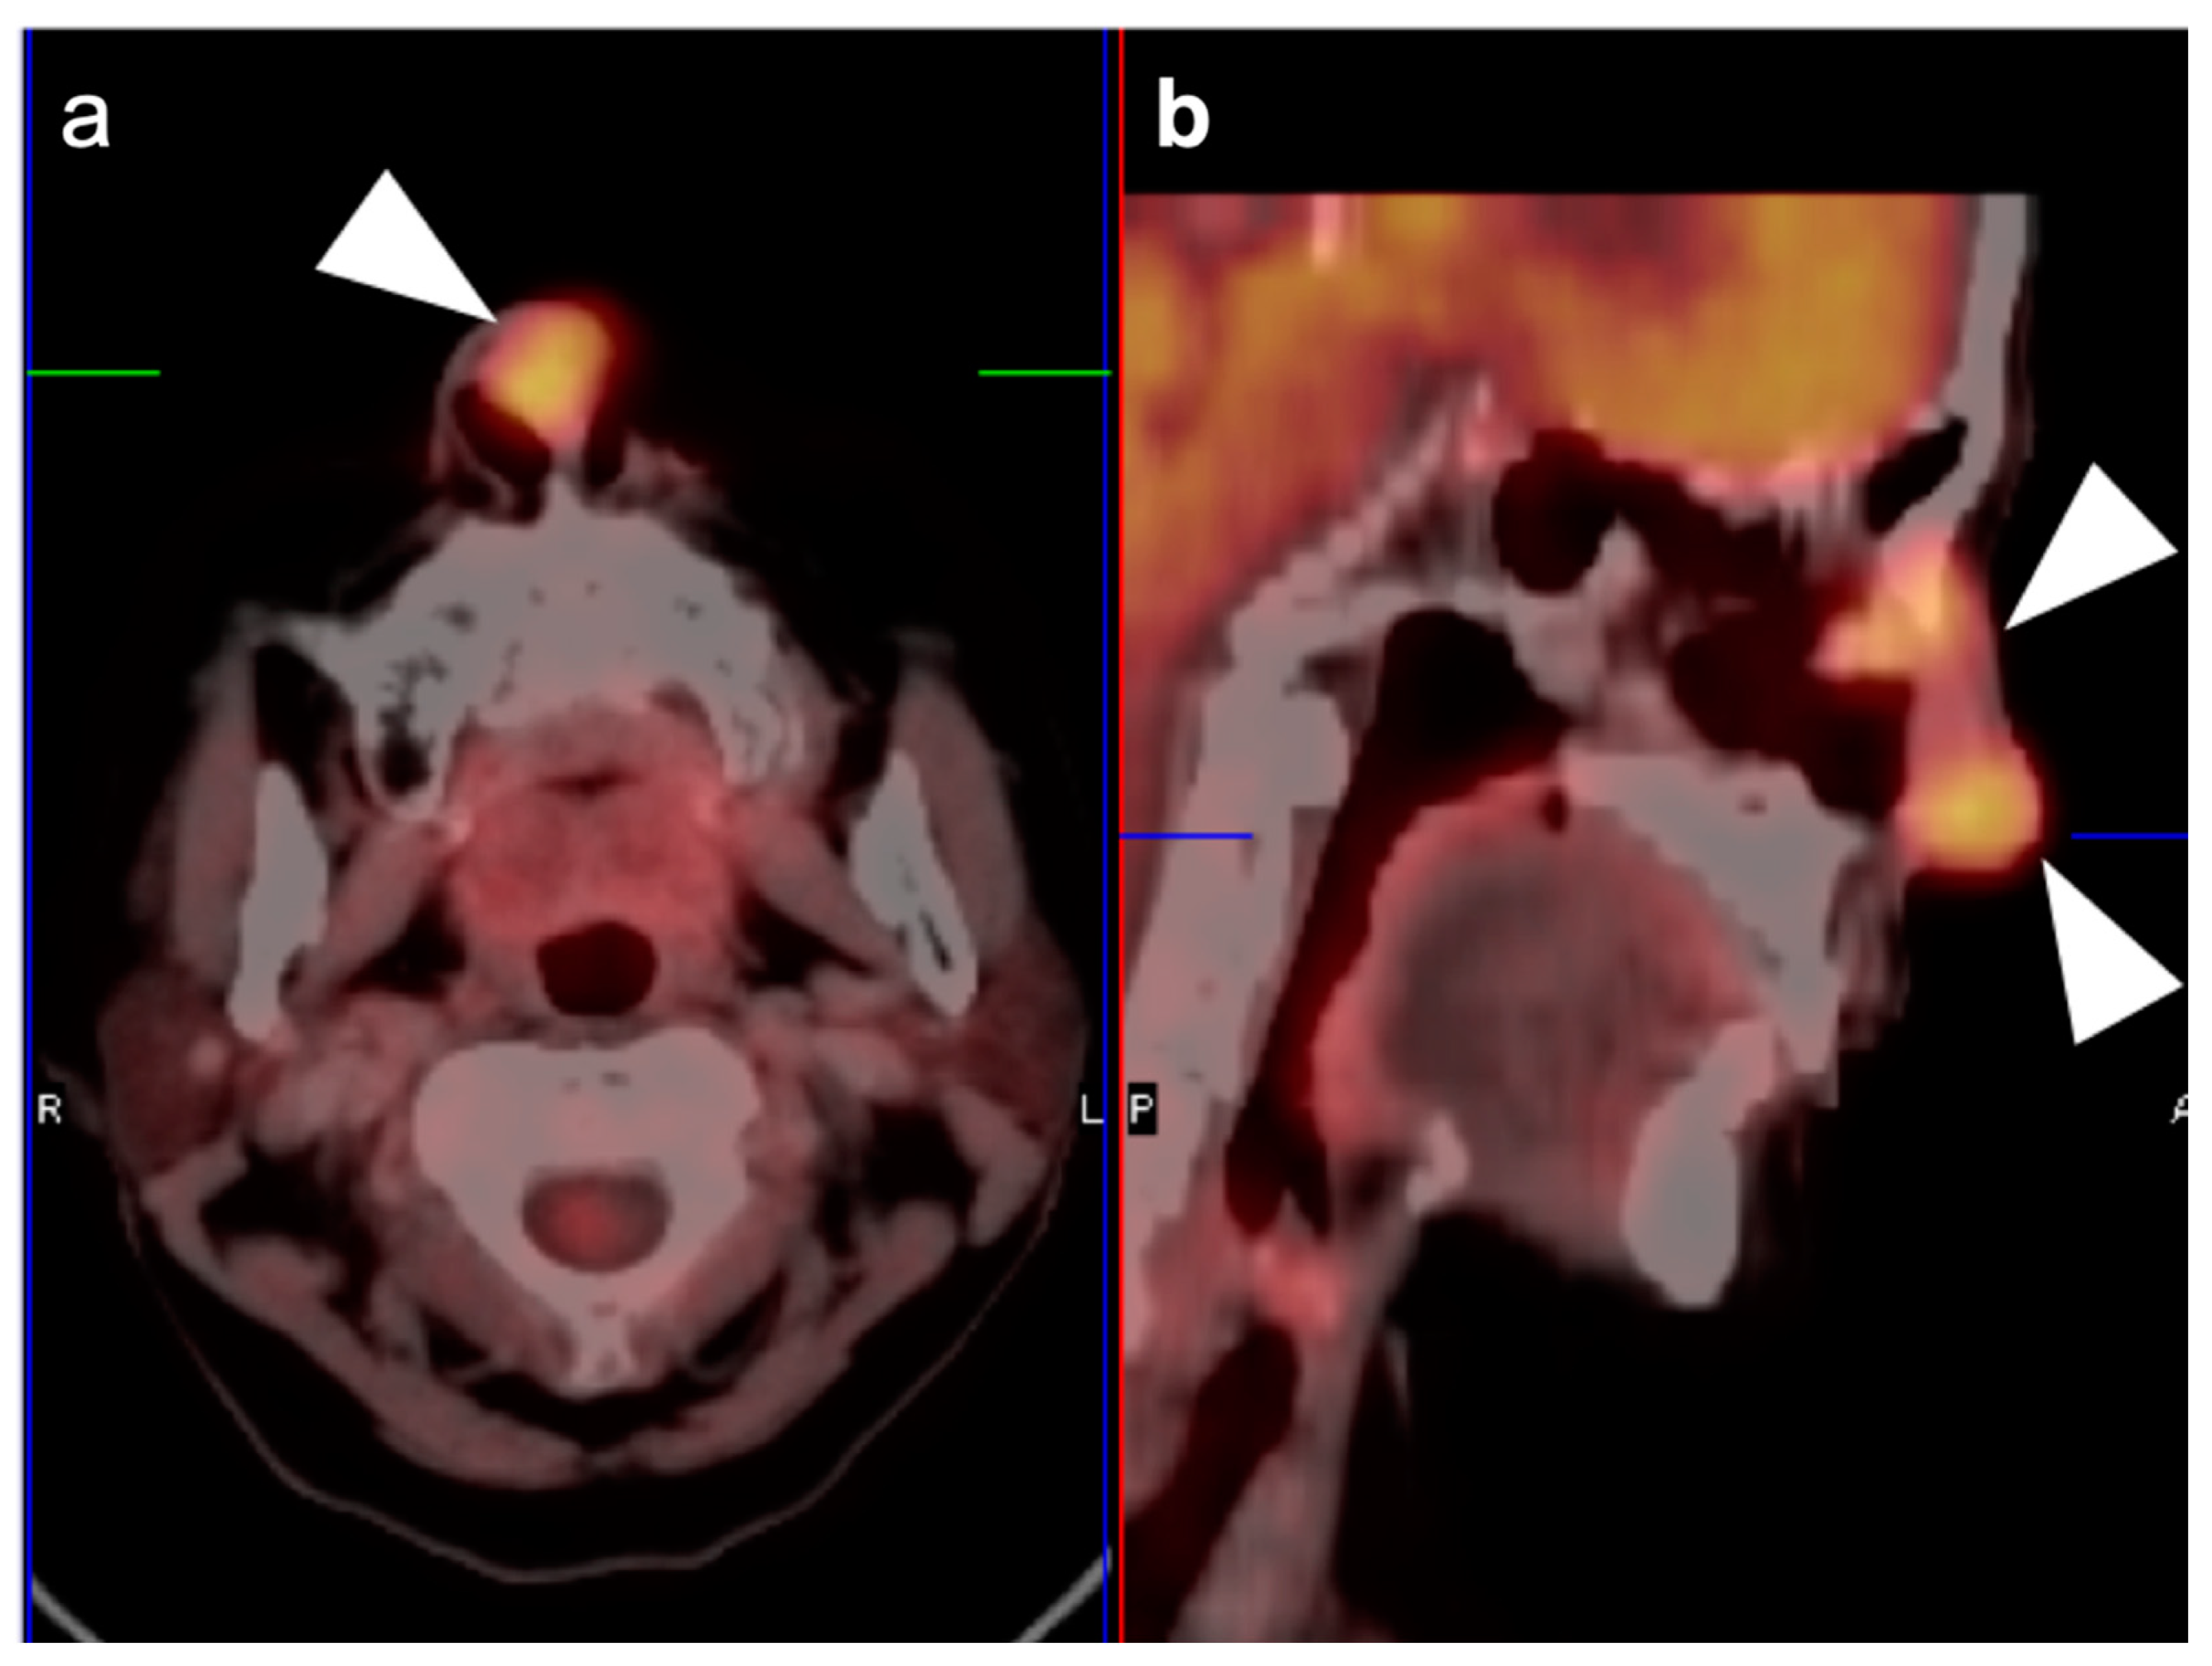

2.3. Nasopharyngeal Carcinoma

2.4. Sinonasal Tumors